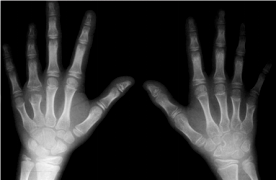

图2-4幼年特发性关节炎活动期

4岁,双手多个指间关节周围软组织肿胀

关节间隙模糊、变窄,右腕骨化中心提

前出现及桡骨过长(骨生长加速所致)